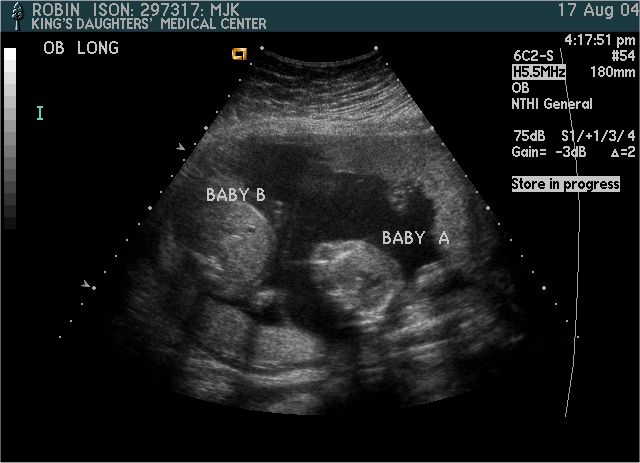

Baby A & B

Pictures from Ultrasound at 20 weeks.